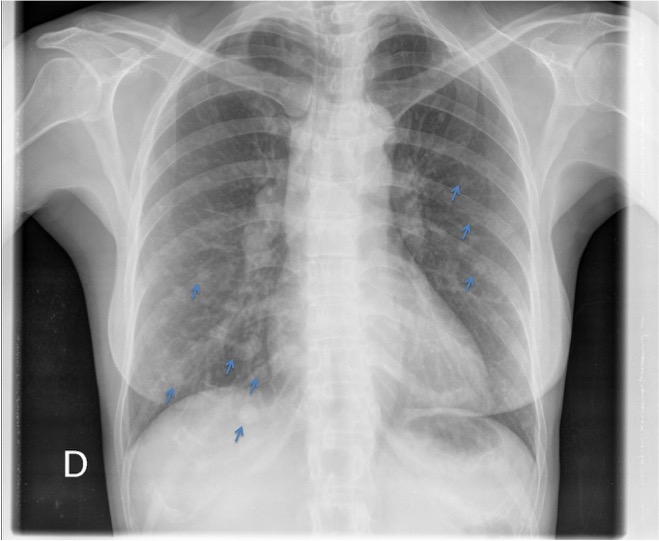

CASO: Paciente con antecedentes de cáncer de útero. Revisión.

Hallazgos:

- Se observan múltiples nódulos en ambos hemitórax. Es el signo de la suelta de globos en relación con metástasis.

SUELTA DE GLOBOS:

Son múltiples nódulos pulmonares bien definidos de distribución bilateral y aleatoria y con diferentes tamaños. Sugieren metástasis pulmonares.

CASO: Disnea.

- Multiples nódulos disperos y bilaterales conformando un claro patrón en suelta de globos.